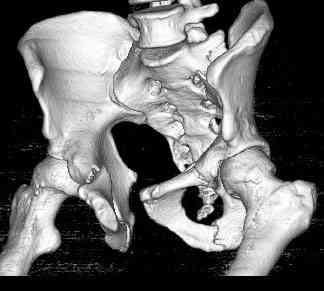

18.12. - отдельное спасибо еще раз А.В.Рункову- больного оперировали (А.В.Рунков) - произведен остеосинтез аппаратом - фиксация за крылья, два стержня в лонные кости и репозиция (почти полная) снимки будут чуть позже.

Дренировали отслойки на бедрах с их санацией. В правой ягодичной области сформировалась зона некроза. Больной "подвешен" за аппарат.